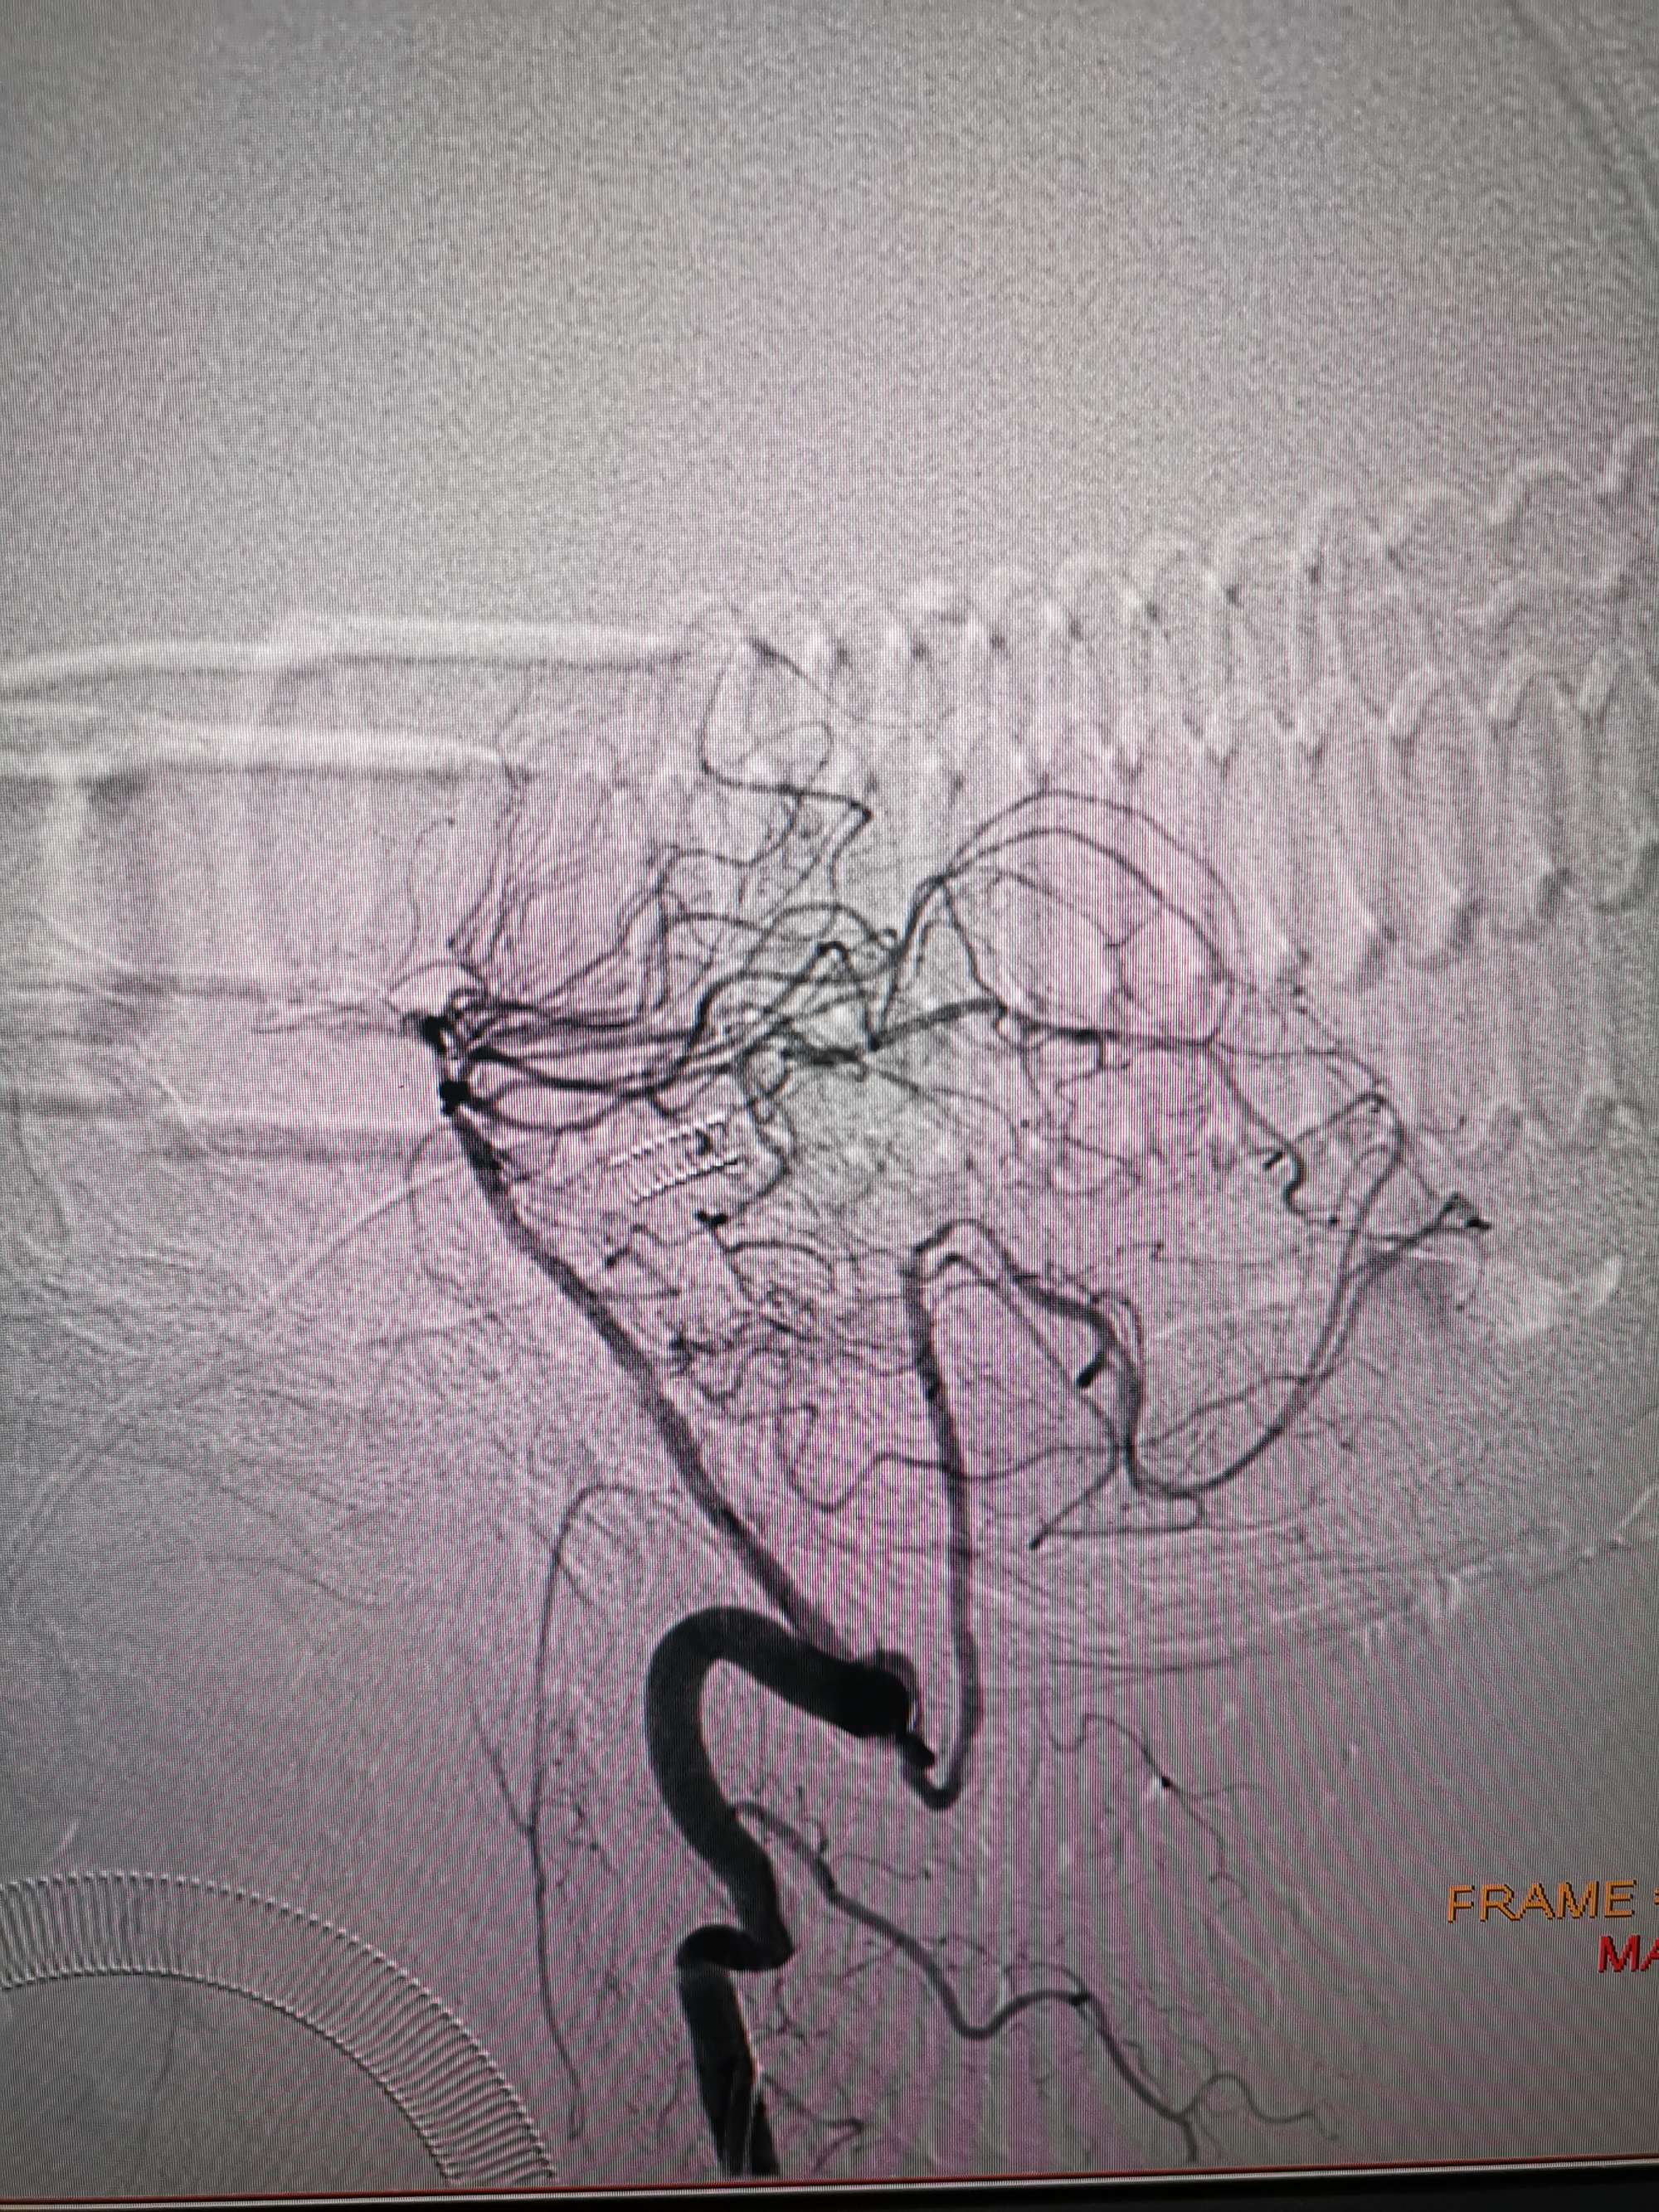

术前再次造影评估

右侧椎动脉穿支供血及左侧PICA供血较入院时略有改善,但改善不明显。故按计划行左侧椎动脉再通术

手术过程

在微导管支撑下先将微导丝和微导管穿过闭塞段,微导管超选造影证实位于基底动脉真腔后更换300cm外周交换导丝,撤出微导管后按从小到大,从远到近的原则行球囊扩张,本例手术选择了1.5✖️15、2.0✖️20、2.5✖️20球囊进行扩张,扩张满意后植入Enterprise支架,手术结束。

术后造影见左侧椎动脉闭塞段管腔恢复正常直径,远端血运良好。